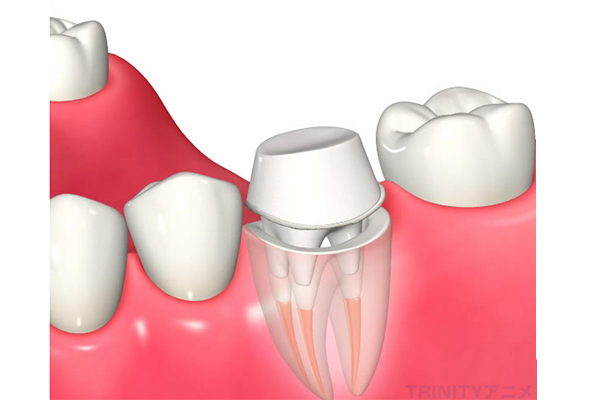

根管充填

根管内部がキレイになり、目立った症状が消失したら、根管の内部を生体親和性のある材料をつめて再感染を防止します。

その際に推奨される材料はMTAセメントですが、これは保険適応外の材料となります。

根管治療が終了したら、噛み合わせや見た目の回復ためにコア(土台)+かぶせ物の治療が必要になり、ここまで行って治療が完了します。

根管治療を成功に導くためには、正確な診断を行い、よく見える状態で感染物を除去し、適切な材料で根管を詰めることが重要です。そして、根管治療が終了後のかぶせ物(クラウン)は再発を防ぐためにはとても重要です。